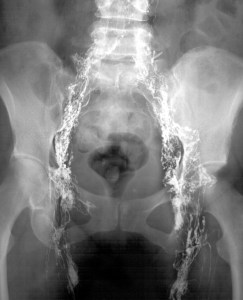

Just like you have blood vessels that carry blood through your body, your lymph system also connects all those nodes in your body to other organs and such through a similar highway, but much smaller. So small in fact, that they lymph vessels are so difficult to see. Unlike a tech finding a good vein to draw blood from by seeing it, in order to find this lymph vessel, you need optical enhancement support to help you see them, and it also cannot be done by just looking through the skin.

The doctor needs to be able to inject an agent into your lymph system to “light it up” on an x-ray to see the entire lymph system. The end result is quite cool, seeing every lymph node glowing in your body. The down side to this process, the substance is injected through your feet, by way of inch long incisions in both feet. Unlike my biopsy, I was going to be awake for this process, lying down on my back, for what seemed like hours. The toe areas on both of my feet would be numbed, and one incision made in my left foot, and unable to locate a vessel in my left foot, a second incision was made just to the right of the other incision. The numbness had begun to wear off just as they were beginning to suture up my feet. As I complained about the pain of that process, I had been advised that I would be sewn up very quickly and it would actually be more painful to inject more numbness with several more sticks. I shut up, and let them finish. I was placed in a wheel chair, and rolled off to x-ray.

The news was good from the results, and just as they were with the blood work, CT scan, the lymphangiogram also showed no signs of Hodgkin’s. This was awesome!